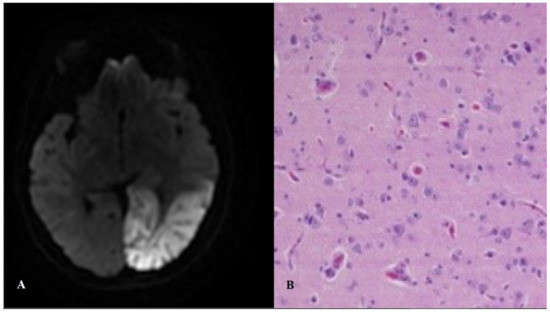

2.4. MELAS: Mitochondrial Encephalopathy with Lactic Acidosis and Stroke-Like Episodes